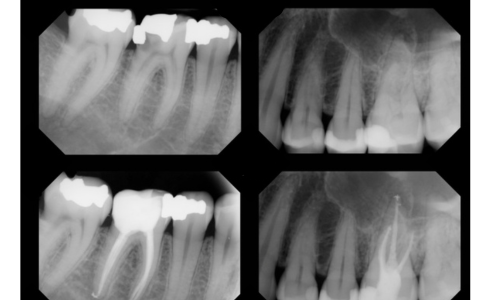

Welcome to Dhanusha Dental Clinic, where your oral health is our priority. Our modern facility boasts RVG X-ray for precise diagnostics, an Endo Motor and APEX LOCATOR for efficient root canal treatments, and five dental chairs to accommodate multiple patients comfortably. With a team of five specialized doctors and a well-trained staff, we offer expertise in general dentistry, orthodontics, periodontics, prosthodontics, and oral surgery. Utilizing dental loupes for precision, we maintain high sterilize standards for a clean environment. Our emergency readiness includes an oxygen cylinder and well-stocked emergency kits. At Dhanusha Dental Clinic, experience top-notch care with cutting-edge technology and a commitment to your well-being.